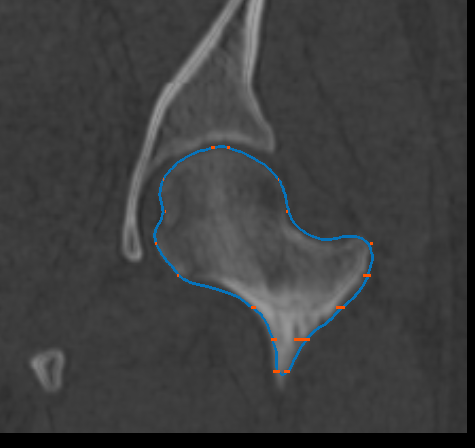

You can generate a mesh surface that fully describes a feature of interest or anatomy after you have created a group of paths that outlines the feature of interest or anatomy (see Creating Groups of Paths). Options for optimizing mesh surface generation can be selected in the Mesh surface tab (see Mesh Surface Settings).

Mesh surfaces are calculated from the point clods on each path and the selected normals.

The mesh generated from the active contour paths appears in the Data Properties and Settings panel.